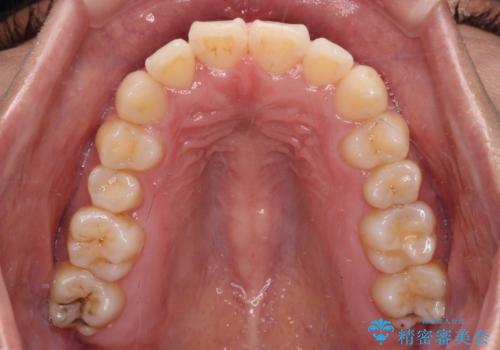

- 前歯のデコボコとクロスバイトを気にして来院された患者様です。

骨格的に下顎が前方位の受け口傾向であり、それが原因でクロスバイトとなっていました。

なお、右奥の歯が180度回転した状態で萌出しており、こちらは改善困難なため、そのままの向きで配列することとしました。